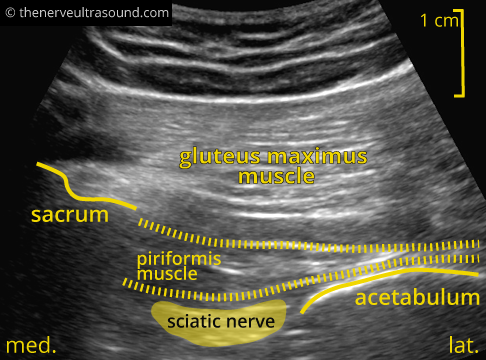

The structures at the gluteal region lie deep, often requiring a lower frequency probe (e.g. 5-8 MHz) to have enough penetration. The piriformis muscle serves as leading structure. Palpation of the border of the sacrum and the greater trochanter helps to identify the expected course of the piriformis muscle. To start off with, it is helpful to place the probe proximal on the ileum with the ultrasound-probe in the orientation of the expected course of the piriformis muscle. Moving distally the cortex of the ilieum bone soon disappears and the piriformis muscle will become visible from its origin on the ventral surface of the sacrum running over the dorsal aspect of the acetabulum to the greater trochanter of the femur.

Passive internal and external rotation of the hip may help to delineate the piriformis muscle.

The sacral plexus with the sciatic nerve lies deep to the piriformis muscle medial to the bone corresponding to the dorsal aspect of the acetabulum. As a variant, the nerve or parts of it can also run through the muscle or dorsal to it.